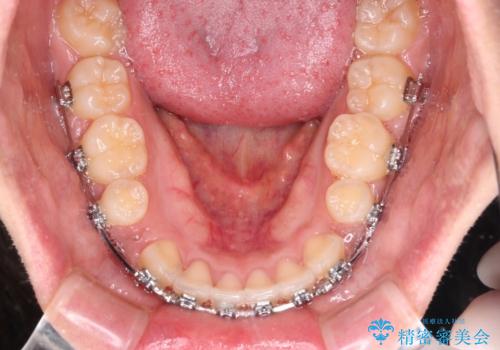

- メタルブラケット

- 3年1ヶ月

上下の前歯が前方に突出していたため、上下左右の第一小臼歯4本を抜歯し、ワイヤー装置にて抜歯矯正を行うこととしました。

上下前歯部の被蓋関係を改善するの時間がかかり、3年間を要することとなりましたが、スッキリとした口元に仕上がりました。